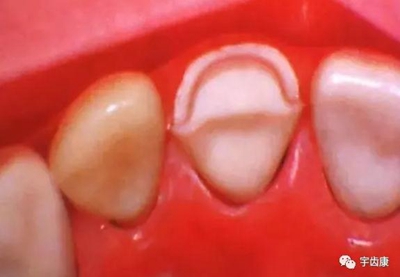

環(huán)抱固位形(主要固位形)

樁固位形(增加固位形和抗力形)